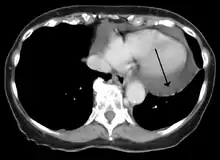

Cardiac CT and MRI scans: cross-sectional imaging with computed tomography (CT) can help localize and quantify the effusion, especially in a loculated effusion (an effusion contained to one area).[11] CT imaging also helps assess for pericardial pathology (pericardial thickening, constrictive pericarditis, malignancy-associated pericarditis).[1] Whereas cardiac MRI is reserved for patients with poor echocardiogram findings and for assessing pericardial inflammation, especially for patients with continued inflammation despite treatment.[4] CT and MRI imaging can also be used for continued follow up on patients.

A CT scan showing a pericardial effusion